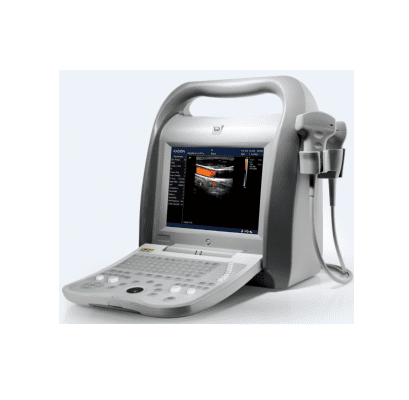

Dcu10 Full Digital Color Doppler Ultrasound Scanner

DCU10 full digital color Doppler ultrasound scanner is available for the diagnosis of abdomen (including GYN and OB), cardiology, vessel and small parts, with the following scanning mode: 2D, CFM, PDI,PW and M to provide the best resolution and sensitivity.

DCU10 Full Digital Color Doppler Ultrasound scanner